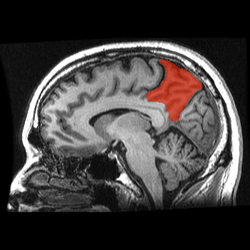

![]() Sagittal MRI slice with the precuneus shown in red. | |

The precuneus is a part of the superior parietal lobule forward of the occipital lobe (cuneus). It is hidden in the medial longitudinal fissure between the two cerebral hemispheres. It is sometimes described as the medial area of the superior parietal cortex. The precuneus is bounded anteriorly by the marginal branch of the cingulate sulcus, posteriorly by the parietooccipital sulcus, and inferiorly by the subparietal sulcus. It is involved with episodic memory, visuospatial processing, reflections upon self, and aspects of consciousness.